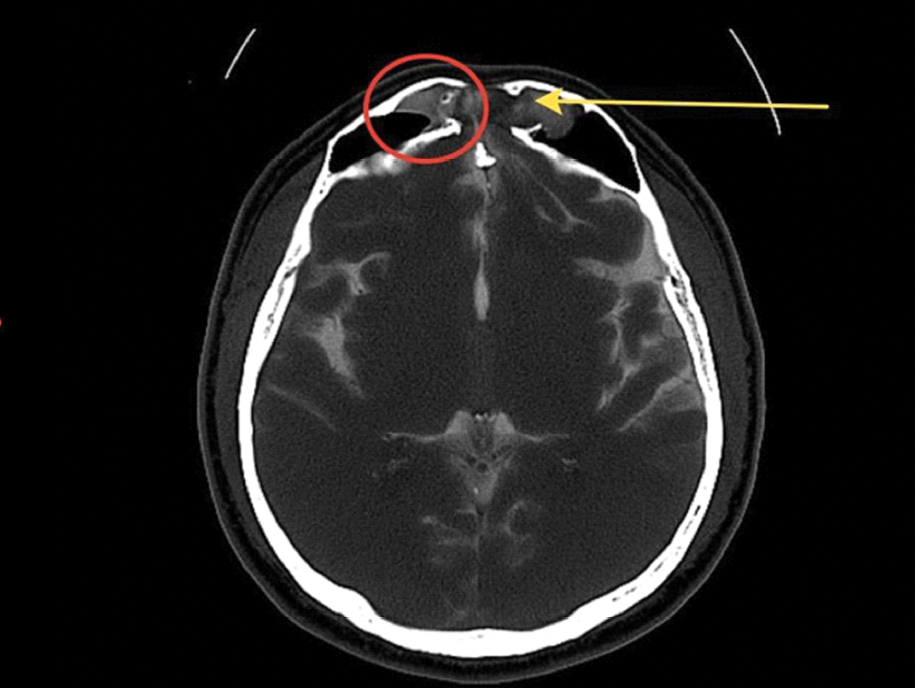

КТ-цистернография (КТ-Ц). При базальной ликворее применяются нейровизуализация ликворопроводящих путей с эндолюмбaльной инъекцией водорастворимых контрастных препаратов [12]. КТ-Ц дает возможность точно локализовать ликворную фистулу, выявить затекание контрастного препарата в придаточные пазухи носа и на основание черепа (рисунки 3, 4 и 5) [13, 34].

Рисунок 4. КТ-Ц с активной назальной ликвореей. Определяется дефект задней стенки лобной пазухи с пролабированием лобных долей (больше левой) в полость лобной пазухи – менингоэнцефалоцеле. В правой лобной пазухе визуализируется контрастный препарат, мигрирующий в полость носа. Желтая стрелка – менингоэнцефалоцеле; красный круг – контрастный препарат в правой лобной пазухе.

Рисунок 5. КТ-Ц с назальной ликвореей; красный круг – контрастный препарат в правой лобной пазухе; красная стрелка – контрастный препарат в полости носа.

КТ-Ц имеет до 96,7% вероятности выявляемости локализации ликворной фистулы при активной и 40% при неактивной ликворее. В остром периоде ЧМТ использование КТ-Ц имеет чувствительность до 56% в связи со сложностью дифференцировки между контрастным препаратом и геморрагическим субстратом в цистернах и в области передней черепной ямки [12, 31].